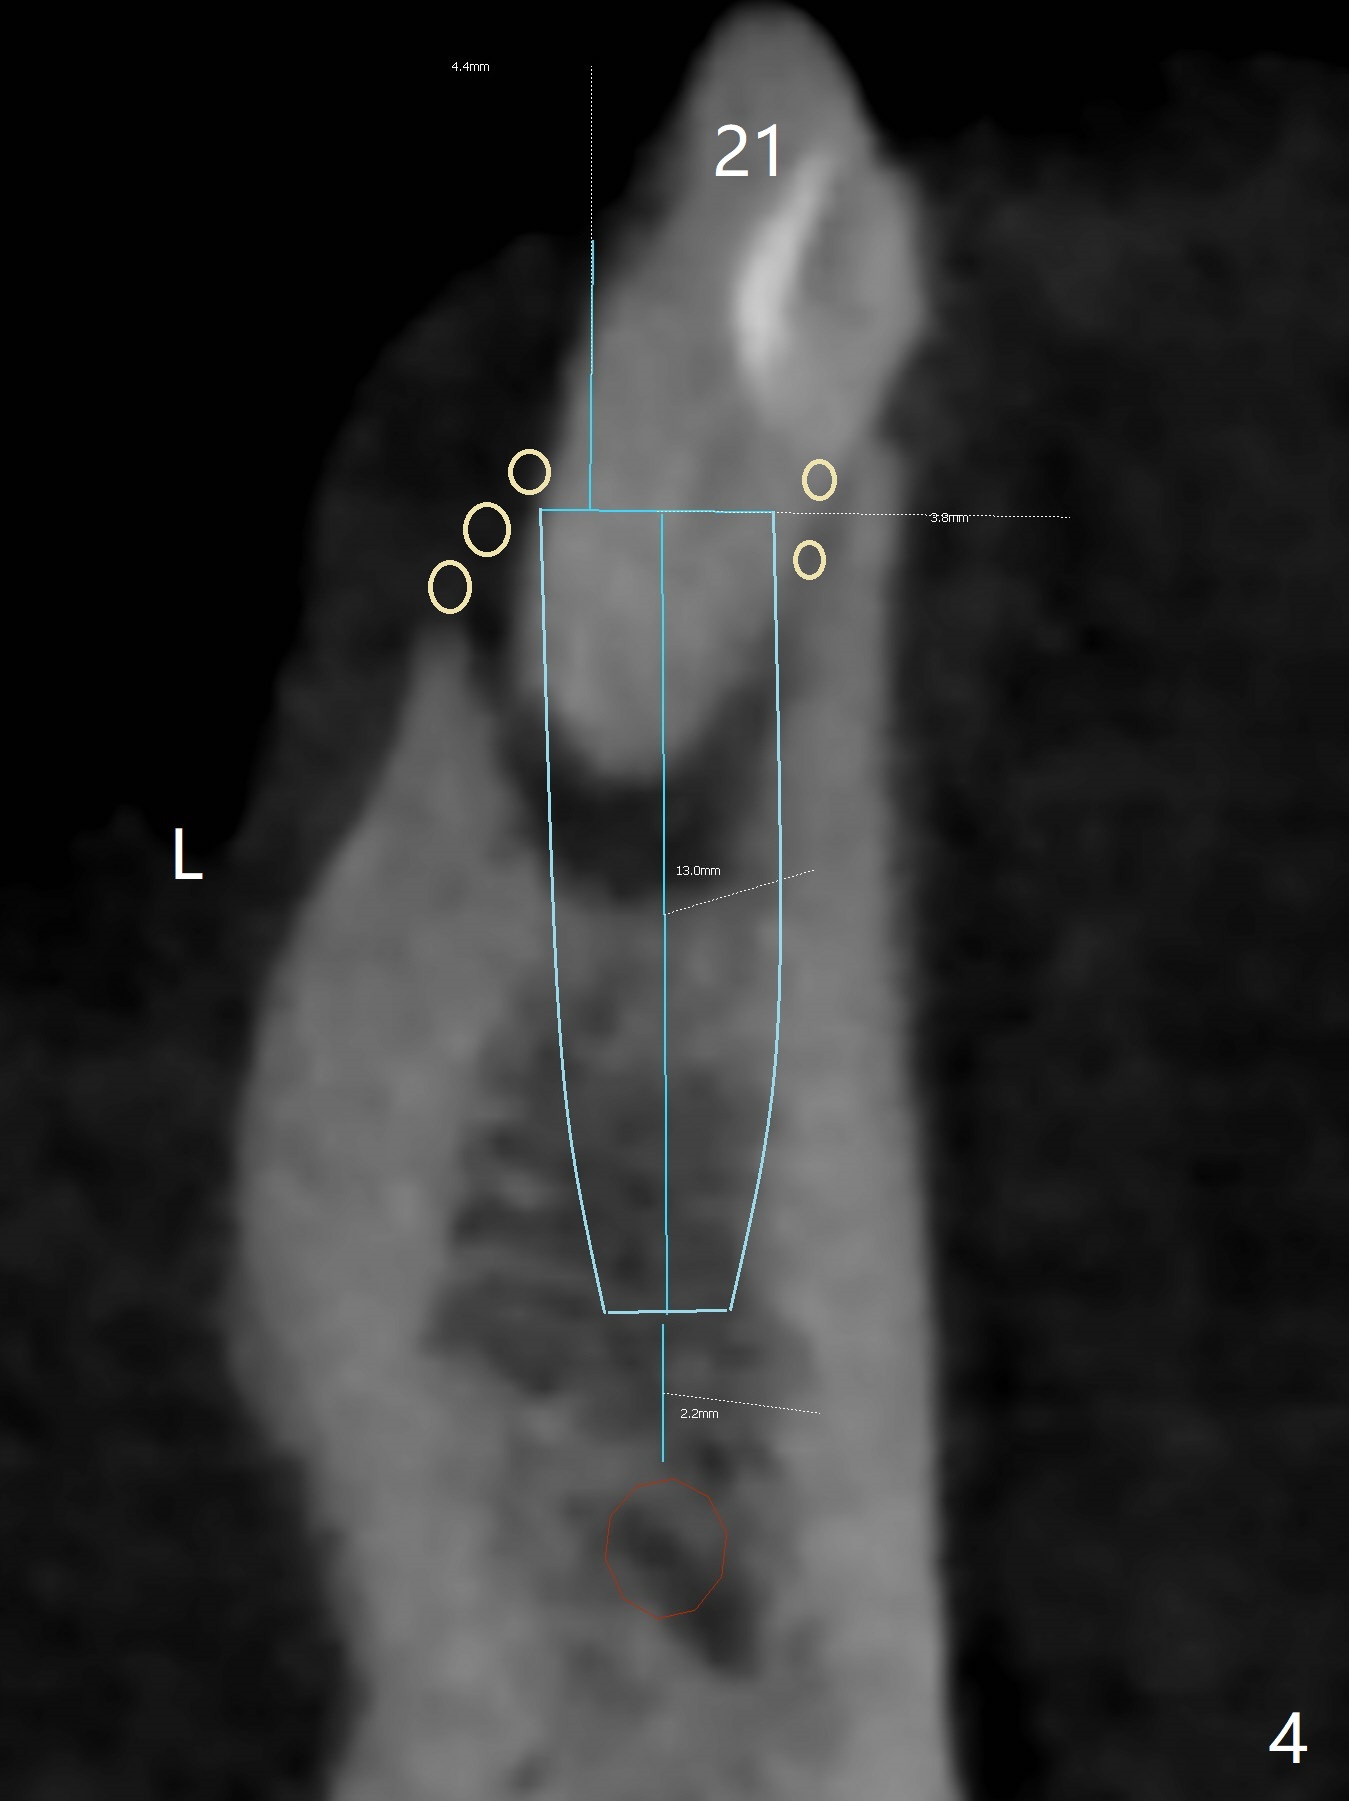

A 54-year-old man has poor dentition, including missing tooth of #19 and residual root at #20 (Fig.1). The lingual crest (Fig.2 (lingual view), Fig.4 (L)) is lower than the buccal one. The Inferior Alveolar Canal (Fig.3 IAC) becomes the Incisive Canal (IC, Fig.4 red circle) after the Mental Loop (Foramen). An implant at #21 will be placed at the level between the buccal and lingual crests (Fig.4) with osteotomy initiated in the middle of the socket. Bone graft is to be placed around the coronal end of the implant (yellow circles).